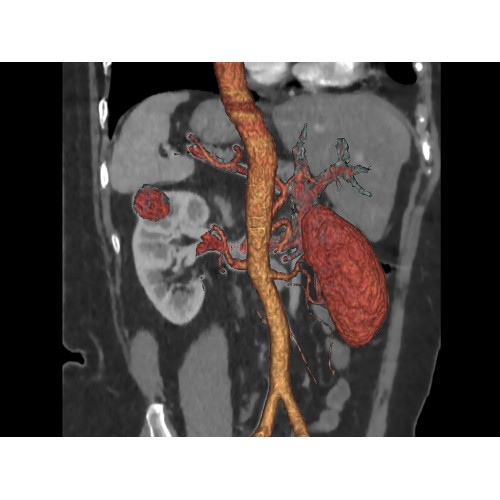

• Широкая область применения: от неврологии до кардиологии и онкологии.

КТ аппарат GE Optima CT520 используется для диагностики широкого спектра заболеваний:

Кардиология

• Неинвазивная оценка состояния коронарных артерий.

• Диагностика атеросклероза и других сердечно-сосудистых патологий.

Онкология

• Раннее выявление новообразований и контроль эффективности лечения.

• Планирование лучевой терапии с высокой точностью.